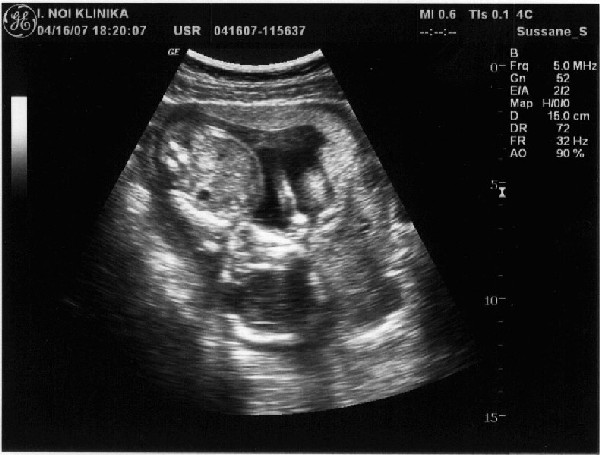

És az UH kép. Fejjel lefelé van. Ha jobban megnézegetitek az első képet látszik hogy az egyik keze az arca előtt van, ökölbe, tehát szerintem cumkizik :).

Kép

A másodikon a kis pisze orra a lényeg.